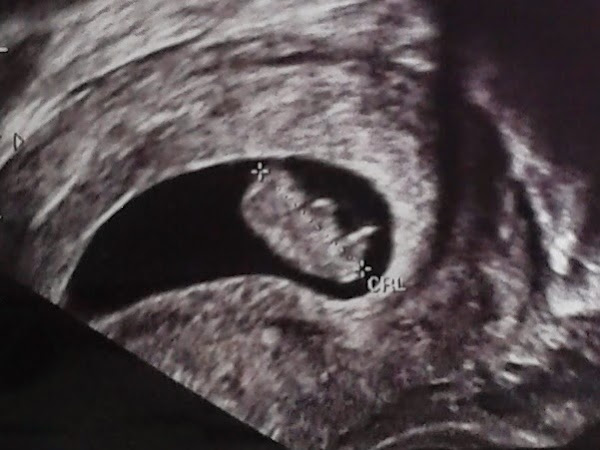

Ecografía primer trimestre de embarazo Fuente: Integra Salud Talavera

Ecografía primer trimestre de embarazo

Fuente: Integra Salud Talavera